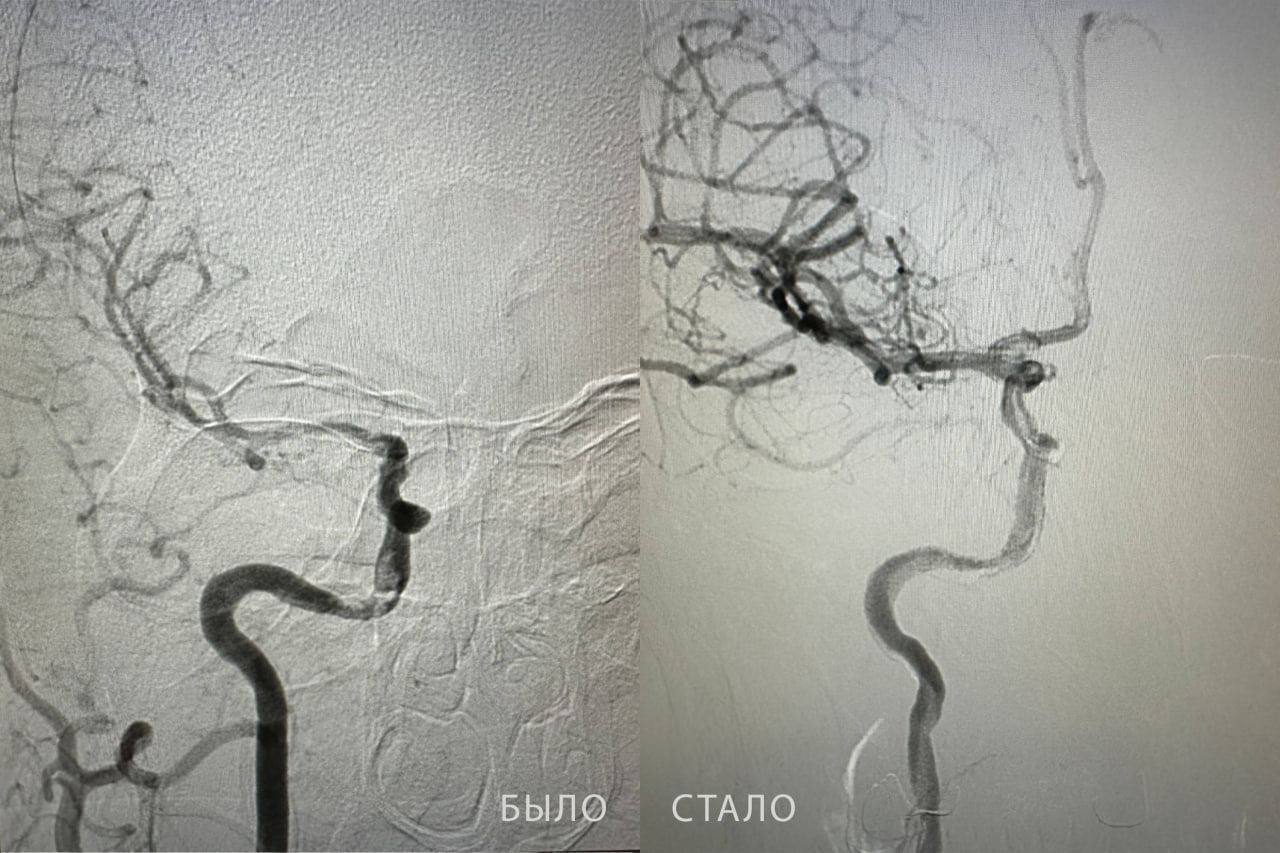

Специалисты в ходе исследования кровеносных сосудов обнаружили тромб в правой внутренней сонной артерии. Ангиохирург Бакназар Абдыкадыров провел сложную операцию, которая длилась более получаса. Он извлек из сосуда тромб длиной почти 2 сантиметра. После высокотехнологичного вмешательства кровоток был полностью восстановлен